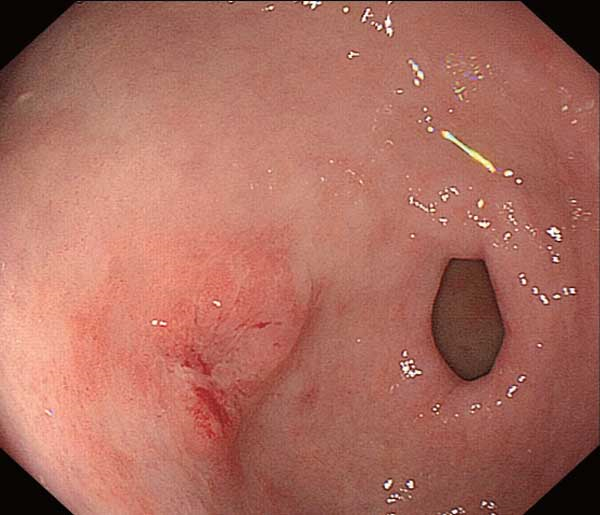

慢性胃炎圖片

慢性胃炎

慢性胃炎的

成人慢性胃炎

中型淺表萎縮慢性胃炎

萎縮淺表性慢性胃炎

萎縮性的慢性胃炎

萎縮性慢性胃炎

萎縮慢性胃炎

萎縮出血性慢性胃炎

輕型淺錶慢性胃炎

輕型淺表型慢性胃炎

縮的慢性胃炎

淺表型慢性胃炎怕

淺表型慢性胃炎

淺表型慢性胃炎萎縮

淺表型糜爛出血慢性胃炎

淺表型糜爛慢性胃炎

輕型慢性胃炎

淺表型慢性胃炎發發

淺表型慢性胃炎好